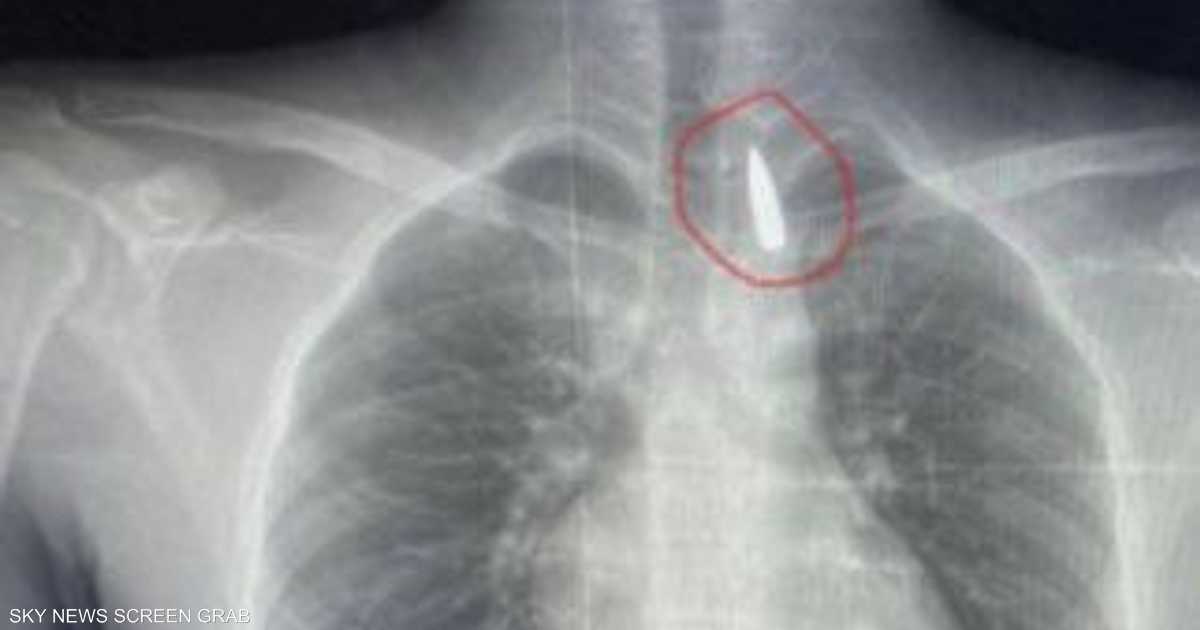

وأوضح عميد كلية الطب جامعة الإسكندرية ورئيس مجلس إدارة المستشفيات الجامعية تامر عبد الله، أن فريق من أطباء قسم جراحة القلب والصدر والتخدير والمعاونين تكمنوا من إجراء جراحة دقيقة بالغة الخطورة لأحد المرضى من قطاع غزة، والذي كان قد تعرض لإصابة بطلق ناري منذ فترة، استقر المقذوف على إثرها داخل تجويف القفص الصدري قرب الشريان الأورطي.

مبينا أن الفريق الطبي نجح، رغم دقة الحالة وتعقيدها، في استخراج المقذوف بأمان بعد عملية جراحية استمرت عدة ساعات داخل المستشفى الجامعي الجديد، حيث خضع المريض بعدها للرعاية الطبية اللازمة، مؤكدا أن حالة المريض حاليا مستقرة وتحت المتابعة الدقيقة من الفريق المختص.

وأكد أن استخراج مقذوف مستقر بالقرب من الشريان الأورطي يتطلب دقة متناهية، وتنسيقا تاما بين تخصصات الجراحة العامة و جراحة الأوعية الدموية، والتخدير، والأشعة، والرعاية المركزة.